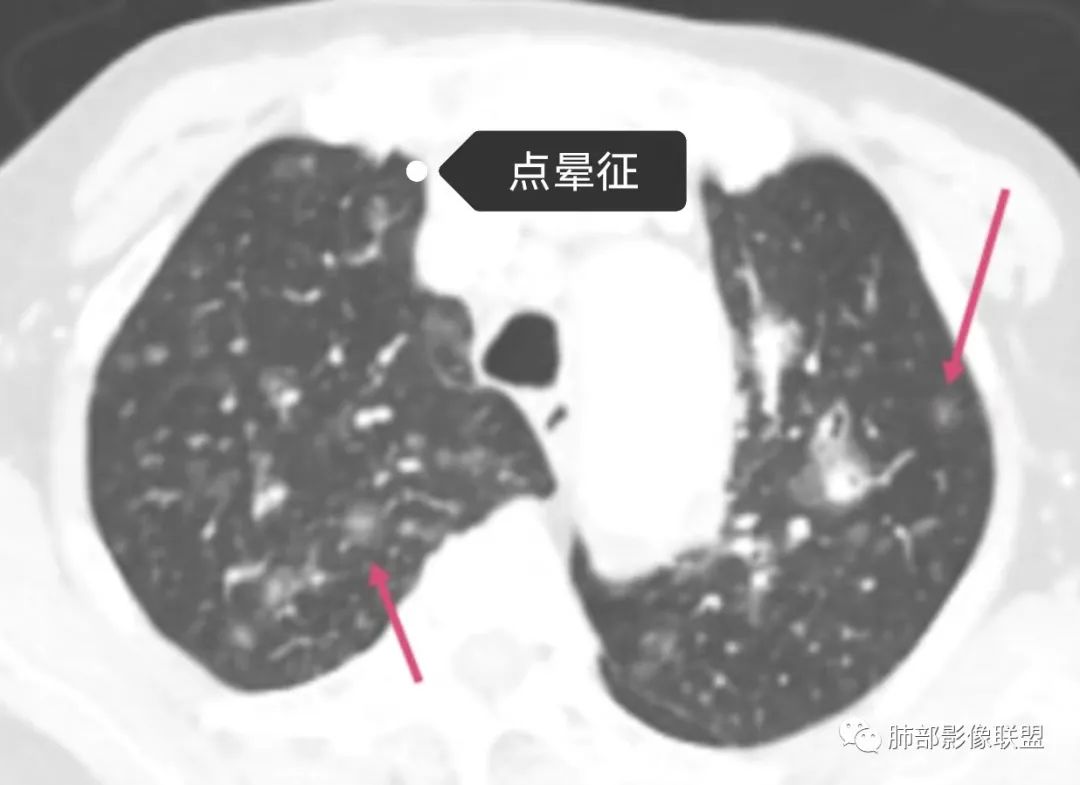

老年女性,双肺支气管管壁增厚,沿血管束走形分布结节及斑片影,复查病灶增多增大,部分呈点晕征改变,腹部左肾盂软组织密度影,周边淋巴结增大。考虑肿瘤并肺内转移,淋巴瘤?鉴别真菌感染,曲霉菌?

82岁女性,反复发热入院,查外周血白细胞升高,抗生素治疗可缓解,支持细菌感染性发热,结合肾脏肿瘤,考虑泌尿系感染发热;CT提示双肺多发毛玻璃影,右下肺多发大结节影,3月复查,双上肺毛玻璃影/混合毛玻璃影增多,部分呈点晕征,右下肺多发肿块,可见支气管穿行,双下肺中轴间质增厚,左肾占位,肺部病变考虑:1.淋巴瘤 2.肾癌肺转移

老年女性,三月来两次发热,第一次白细胞计数升高、贫血。第二次白细胞计数不高,LDH升高、低蛋白血症。肺内进行性增多的结节及斑片影,结节见点晕征,斑片影位于支气管血管束,部分支气管壁外见边界模糊的斑片影。有左肾病变。考虑血管炎可能性大。(诊断关键点可能是:点晕征 支气管血管束的斑片影 肾脏病变 第二次发热但白细胞计数不高)

点晕征疾病谱:

1.肿瘤

血管原发肿瘤:血管肉瘤(右房)、上皮样血管内皮瘤、血管内淋巴瘤(大B)

转移瘤:消化生殖系统转移,关注绒癌、恶黑、肠癌

2.感染

真菌:荚膜组织胞浆菌

病毒:疱疹病毒

结核

3.血管炎

4.寄生虫病

5.PCH/PVOD